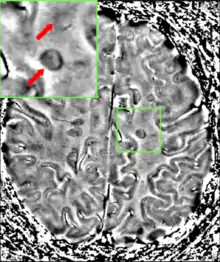

يتم تشخيص مرض التصلب المتعدد بناءً على العلامات والأعراض الموجودة، بالإضافة إلى التصوير الطبي والفحوصات المخبرية الداعمة.[19] قد يكون تأكيد المرض صعباً، خاصة في المراحل المبكرة، حيث قد تتشابه علامات المرض وأعراضه مع أمراض أخرى.[4][38] تعتبر معايير ماكدونالد أكثر الطرق المستخدمة في تشخيص مرض التصلب اللويحي، وهي تركّز على على الأدلة السريرية والمخبرية والإشعاعية لوجود الآفات في أوقات مختلفة في مناطق مختلفة[12] كما تعتبر معايير شوماخر ومعايير بوزر الأكثر أهمية تاريخياً.[39] تتيح المعايير السابقة التشخيص غير الباضع، إلا أن البعض يشير إلى أن الدليل القاطع الوحيد على وجود المرض هو إجراء تشريح بعد الوفاة أو أخذ خزعة من الموضع الذي تم التأكد من وجود آفات نمطية للتصلب المتعدد فيه.[4][40][41] قد تكون البيانات السريرية وحدها كافية لتشخيص التصلب المتعدد إذا تعرّض المريض لهجمات منفصلة من الأعراض العصبية التي تميّز المرض.[40] في المرضى الذين يسعون للحصول على رعاية طبية بعد هجمة واحدة فقط، فإن الأمر يحتاج إلى اختبارات أخرى لإجراء التشخيص. أكثر الأدوات التشخيصية استخداماً هي التصوير العصبي، وتحليل السائل الدماغي الشوكي والاستجابات المستثارة. قد يظهر التصوير بالرنين المغناطيسي للمخ والنخاع الشوكي مناطق مزالة الميالين (ندوب أو لويحات). يمكن إعطاء الغادولينيوم من خلال الوريد كمادّة تباين لإلقاء الضوء على اللويحات النشطة ولإظهار وجود آفات قديمة غير مترافقة بأعراض إثناء إجراء التقييم، عن طريق الإلغاء.[40][42] يمكن أن يقدم اختبار السائل الدماغي الشوكي الذي تم الحصول عليه من البزل القطني الدليل على وجود التهاب مزمن في الجهاز العصبي المركزي. يُفحص السائل الدماغي الشوكي للحصول على الشرائط قليلة الأنسال من الغلوبولين المناعي G بواسطة الرحلان الكهربائي، والتي تعتبر واسمات التهابية توُجد لدى 75% - 85 % من الأشخاص المصابين بالتصلب المتعدد.[40][43] قد يستجيب الجهاز العصبي في حالة الإصابة بالتصلب المتعدد بصورة أقل نشاطاً لتحفيز العصب البصري والخلايا العصبية الحسية بسبب زوال الميالين من تلك الممرات. يمكن فحص هذه الاستجابات الدماغية باستخدام الاستجابات المرئية المستثارة والاستجابات المستثارة الحسية.[44]